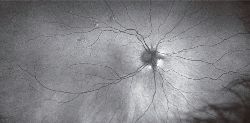

OCTA

OCT Angiographyの導入

Zeiss社製OCT(シラスHD-OCT) を新機種に切り替えました

OCTアンギオグラフィーを行うことができます

(2016年2月より)

従来のOCT画像は眼球内の網膜や脈絡膜の構造や病変を三次元的に描出できる画期的な検査器械でしたが、測定技術と精度の向上により血液の流れている場所を検出し、網脈絡膜内あらゆる層ごとに三次元で再構築できるようになりました。

これをOCT Anigiographyと呼びますが、これにより得られる情報は従来なら静脈注射による造影検査でしか分からなかった血管内の血流などの情報を描き出すことができるようになりました。

この技術は画期的で、ショックなどのリスクのある造影剤を使用することなく、散瞳(点眼薬で瞳を広げること)もせずに短時間で網脈絡膜血管の描出が可能であるうえ、 蛍光眼底造影では不可能だった網膜血管の表層、 深層の層別の分析も可能となりました。

これにより患者さんの負担も大きく減少し診断、治療がスムーズに行うことができるようになりました。 LinkIcon 戻る